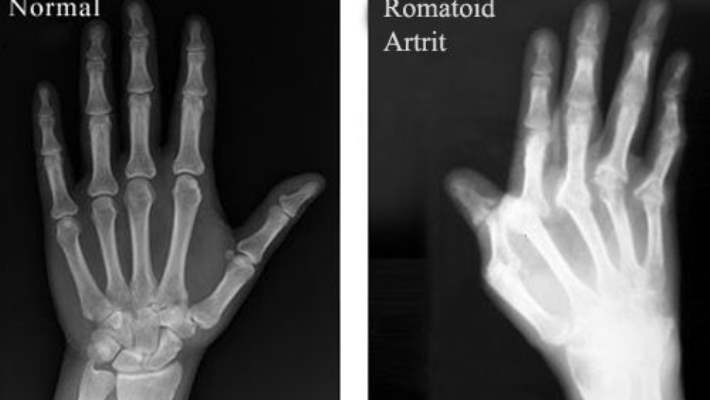

Bilek egzersizleri resimli. ön kol kasları en iyi şekilde nasıl çalıştırılır. Egzersizler eklem tutukluğunu açmak kas ve bağları esnetmek kasları güçlendirmek denge ve koordinasyonu arttırmak gibi amaçlarla yapılır her hareket herkes için uygun olmayabilir. Ayak bileği güçlendirme ayak bileğinin sakatlanması veya incinmesi halinde ayak bileği eklemlerini güçlendirilmesi için uygulanan egzersiz programıdır. Osteoartrit oa yaşla birlikte sıklığı artan ve ağrı ve sakatlıklara neden olarak bireyin yaşam kalitesini önemli ölçüde bozabilen dejeneratif bir eklem has.